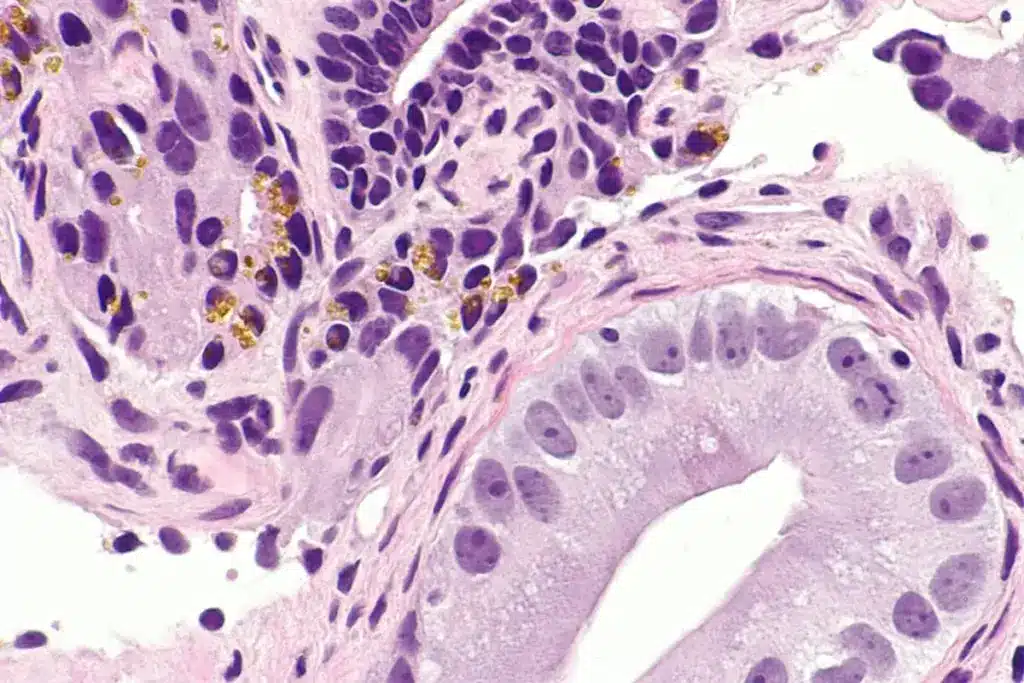

A prostate biopsy takes small tissue samples from the prostate gland with a special needle. It can be done through the rectum or perineum. Then, the samples are checked under a microscope for cancer.

Understanding prostate biopsy results is key. The process gives vital info about cancer presence or absence. This info is critical for patient care planning.

What to Expect in Results

Biopsy results show if cancer is present. If so, they include a Gleason score. This score shows how cancer cells look like normal cells. A higher score means more aggressive cancer.

The report may also show how much cancer is in the samples. This info helps in cancer staging and treatment planning.

Several things can change how accurate biopsy results are. One big factor is the accuracy of MRI in diagnosing prostate cancer. MRI-guided biopsies can find cancer more accurately by targeting specific areas.